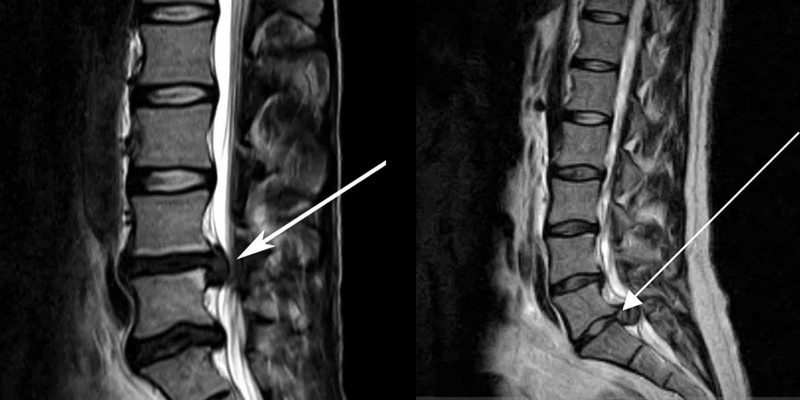

• протрузия и смещение межпозвоночных дисков (грыжа);

• оценка степени, направления и характеристик грыжевого выпячивания.

Заболевания и травмы позвоночника